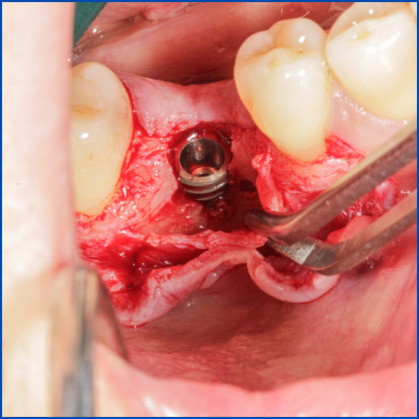

Kist nedeni ile çene kemiğinde defekt oluşmuş vakamıza sert ve yumuşak doku ogmentasyonu uyguladık